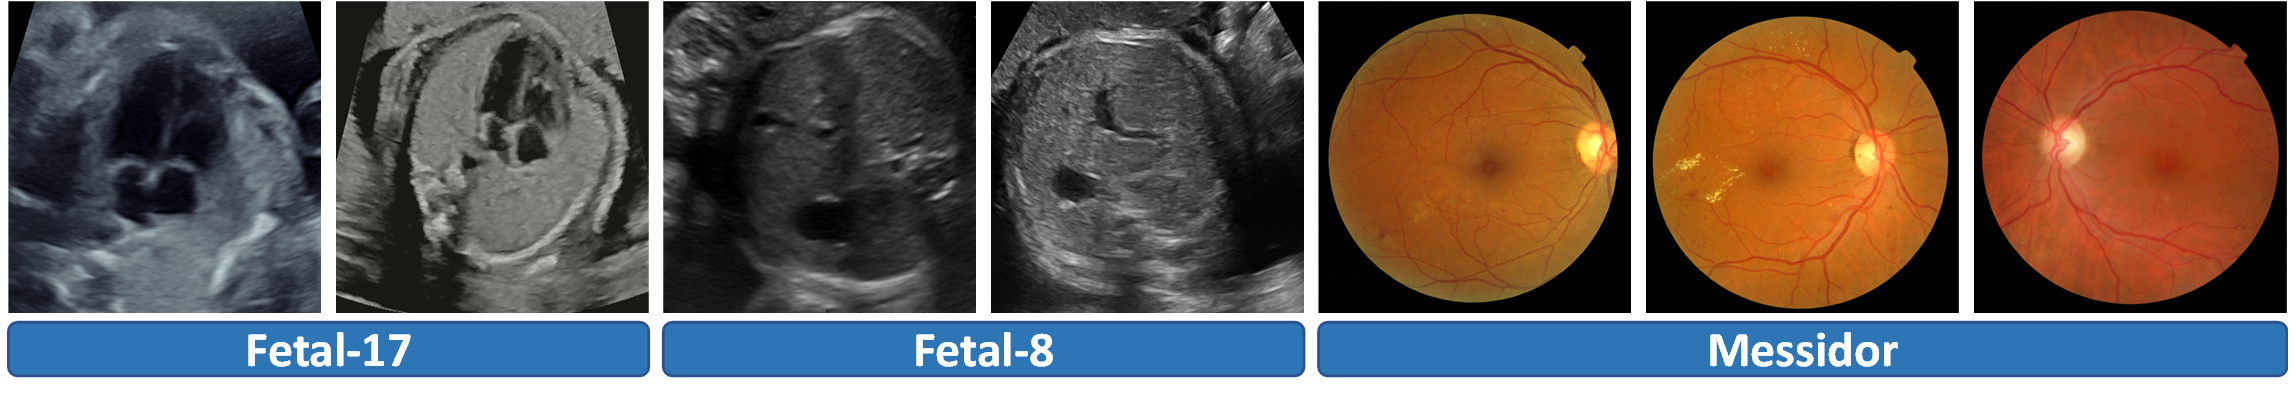

Domain shift (see Fig. 1) may cause deep classifiers to struggle in making plausible predictions during testing [14]. This risk seriously limits the reliable deployment of these deep models in real-world scenarios, especially for clinical analysis. Collecting data from the target domain to retrain from scratch or fine-tune the trained model is the potential solution to handle the domain shift risks. However, obtaining adequate testing images with manual annotations is laborious and impracticable in clinical practice. Thus, different solutions have been proposed to conquer the problem and improve the model robustness.

Refer to caption

Figure 1: From left to right: 1) four-chamber views of heart from Vendor A&B, 2) abdomen planes from Vendor C&D, 3) fundus images with diabetic retinopathy of grade 3 from Center E-G. Appearance and distribution differences can be seen in each group.

Materials and Implementations. We validated the FTTA framework on three classification tasks, including one private dataset and two public datasets (see Fig. 1). Approved by the local IRB, the in-house Fetal-17 US dataset containing 8727 standard planes with gestational age (GA) ranging from 202020 to 24+6superscript24624^{+6} weeks was collected. It contains 17 categories of planes with different parts, including limbs (4), heart (4), brain (3), abdomen (3), face (2), and spine (1). Four 10-year experienced sonographers annotated one classification tag for each image using the Pair annotation software package [12]. Fetal-17 consists of two vendors (A&B) and we conducted bidirectional experiments (A2B and B2A) for method evaluation. The Maternal-fetal US dataset named Fetal-8 (GA: 18-40 weeks) [2]111https://zenodo.org/record/3904280#.YqIQvKhBy3A contains 8 types of anatomical planes including brain (3), abdomen (1), femur (1), thorax (1), maternal cervix (1), and others (1). Specifically, 10850 images from vendors ALOKA and Voluson (C&D) were used for bidirectional validation (C2D and D2C). Another public dataset is a fundus dataset named Messidor, which contains 1200 images from 0-3 stage of diabetic retinopathy [3]222https://www.adcis.net/en/third-party/messidor/. It was collected from three ophthalmologic centers (E, F&G) with each of them can treated as a source domain, allowing us to conduct three groups of experiments (E2FG, F2EG and G2EF). Dataset split information is listed in Table 1.